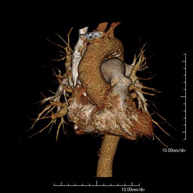

Prueba diagnóstica que consiste en el estudio de la aorta torácica (principal arteria del tórax) mediante el empleo de un equipo de TC (Tomografía Computarizada). Esta técnica requiere el empleo de contraste yodado, y proporciona imágenes de alta definición anatómica. El uso del TCMD (TC Multidetector) acorta el tiempo de exploración, disminuye la dosis de radiación y mejora la calidad de la imagen. Gracias a los múltiples detectores, en determinados estudios se puede acoplar la obtención de la imagen con el latido cardíaco, técnica que permite el estudio de la válvula aórtica y de la raíz de la arteria aorta (primeros centímetros), donde el latido del corazón suele provocar múltiples artefactos de movimiento. - Angio –TC Artèries pulmonars (estudi TEP, Tromboembòlia pulmonar)

Prova diagnòstica que consisteix en l'estudi de l'aorta toràcica (principal artèria del tòrax) mitjançant l'ús d'un equip de TC (Tomografia Computeritzada). Aquesta tècnica proporciona imatges d'alta definició anatòmica. En la majoria de casos és necessari l'ús de contrast iodat. L'ús del TCMD (TC Multidetector) escurça el temps d'exploració, disminueix la dosi de radiació i millora la qualitat d'imatge. Gràcies als múltiples detectors en determinats estudis es pot afegir l'obtenció de la imatge amb el batec cardíac, tècnica que permet l'estudi de la vàlvula aòrtica i de l'arrel de l'artèria aorta (primers centímetres), on el batec del cor acostuma a provocar falses imatges a causa del moviment. - Angio TC d'artèries pulmonars (estudi Tep, tromboembolisme)

L'Angio TC cardíac o la coronariografia no invasiva és una prova diagnòstica que consisteix en l'estudi de les artèries del cor o artèries coronàries mitjançant l'ús d'un equip de TC Multidetector d'última generació (64 corones o files de detectors) i de contrast iodat amb l'obtenció d'imatges bi i tridimensionals. El TC Multidetector 64 o TCMD64 permet una adquisició d'imatges tan ràpida que es poden valorar les artèries coronàries amb alta precisió anatòmica (estrenyiments o estenosis, calcificacions, variants anatòmiques, etc.), ja que, gràcies a la seva rapidesa, evita les falses imatges que provoca el moviment constant del cor (triga menys de deu segons en adquirir unes 1000 imatges). La informació obtinguda d'un tractament en estacions de treball amb programes especialitzats en la reconstrucció de les artèries coronàries que permeten valorar el nombre, la localització i les característiques de les lesions. Tota aquesta informació s'obté de manera no invasiva: només es necessita la punció d'una vena perifèrica (en el braç). És necessari que la freqüència cardíaca no superi els 75 batecs per minut, per això els pacients han de realitzar un tractament previ amb un fàrmac betabloquejant. - Angio TC d'aorta abdominal